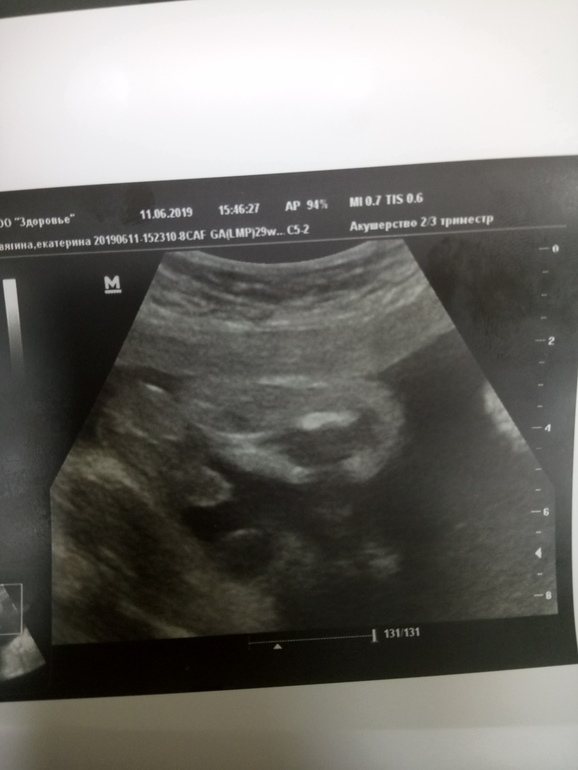

А это узи сегодня

11.06.2019